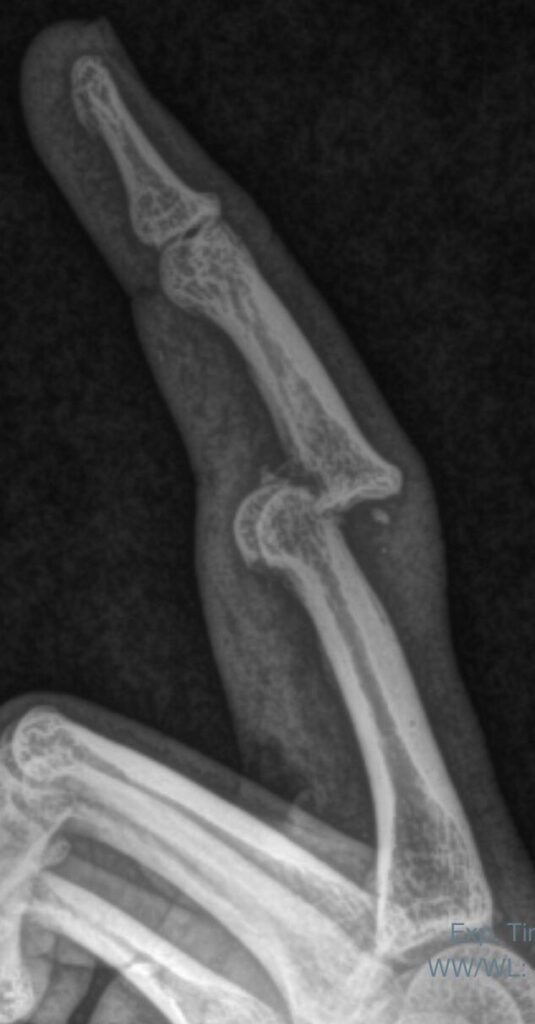

Fracturas y luxofracturas en la mano – Asociación Argentina de Cirugía de la Mano